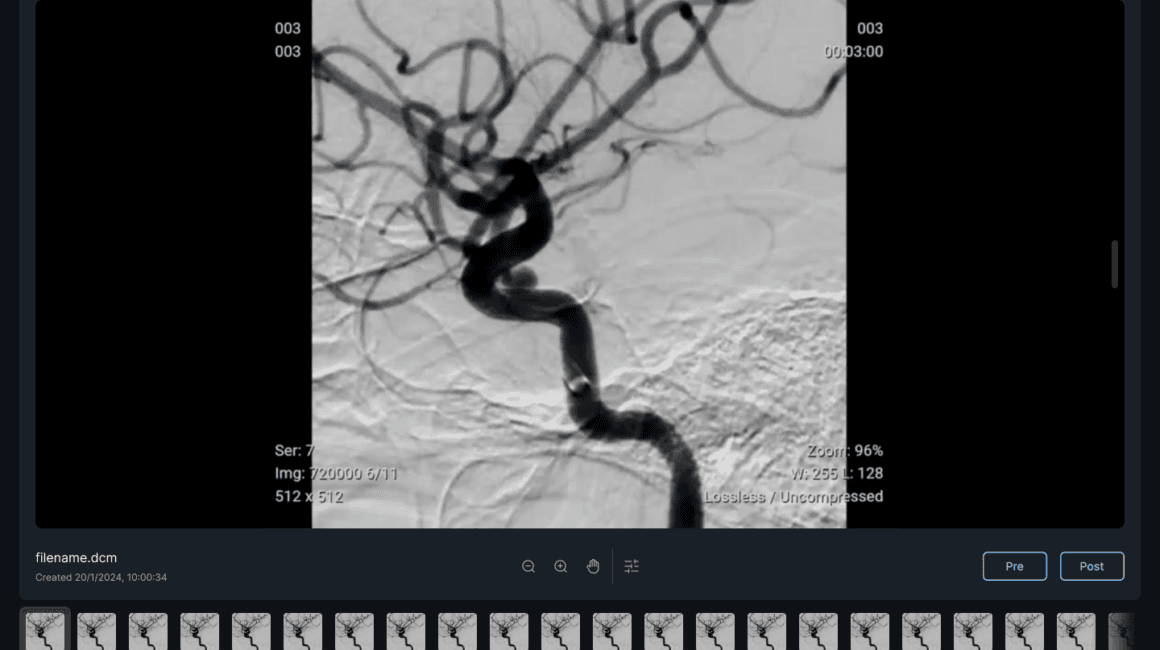

QAS.AI menawarkan perangkat lunak berbasis kecerdasan buatan yang revolusioner, dirancang khusus untuk mendukung prosedur bedah neurologi. Perangkat lunak ini mampu mendeteksi area aliran darah yang tidak memadai di otak selama operasi, serta memprediksi efektivitas koreksi aneurisma enam bulan setelah embolisasi. Dengan teknologi canggih ini, QAS.AI membantu para ahli bedah dalam membuat keputusan yang lebih tepat dan meningkatkan hasil operasi, menawarkan alat yang vital dalam penanganan kondisi kritis otak.